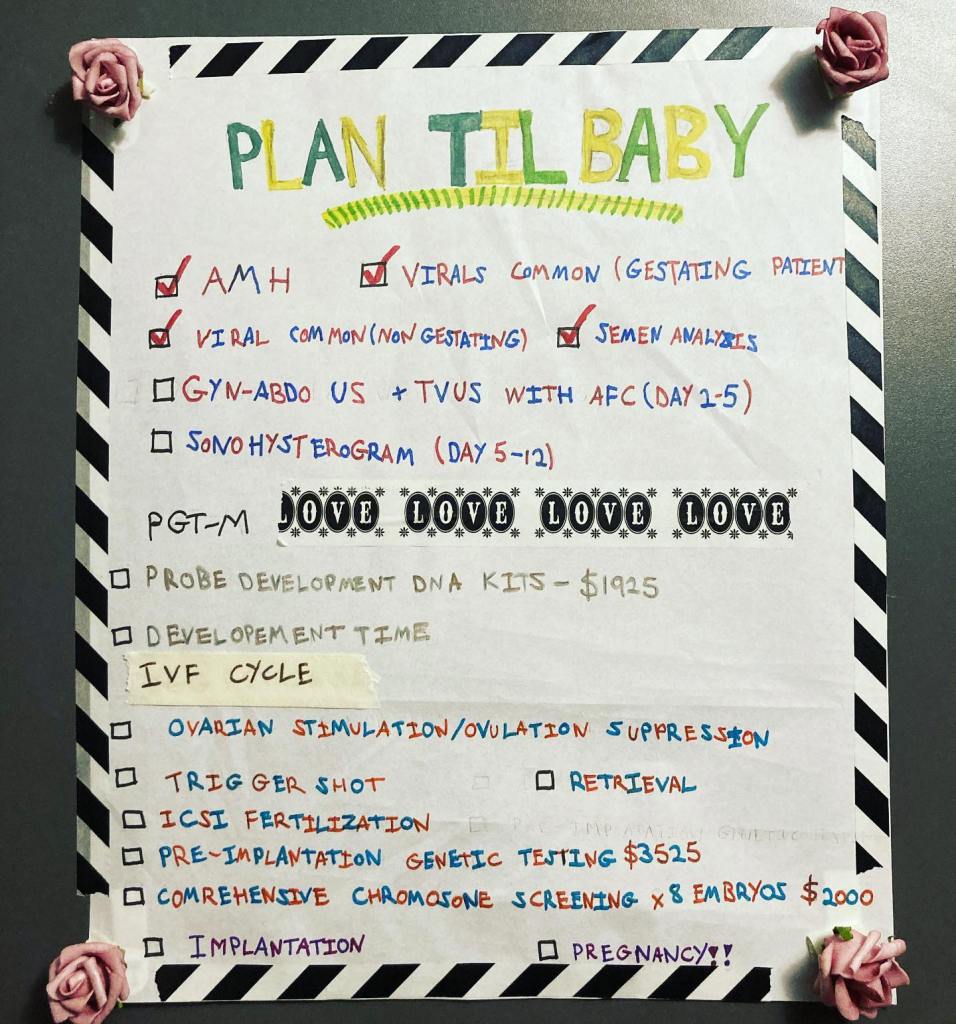

I couldn’t do it again. I decided that the next time I got pregnant, I’d do IVF. I’d get the embryos tested before implantation. I couldn’t lose another baby.

We tried IVF. IVF is hard and expensive, but in Ontario they cover one cycle of it. With work covering my drugs, the real problem was the extra expense of getting the embryos tested. It costs eight grand on top of everything else and takes three months to set up.

They sequence you and your parents and your partner, and they make what they call a probe. They do this before they remove the eggs. Then they’ll test all the eggs using the probe and you have the option to discard any that come up positive. It’s a rotten numbers game. They predicted they’d extract 8 eggs, and 4 would be non-viable for whatever reason, and 1 or 2 might be negative for FAP and viable. Or all 8, or none. I might spend eight thousand dollars to have no viable eggs. There’s no way to know until you do it.